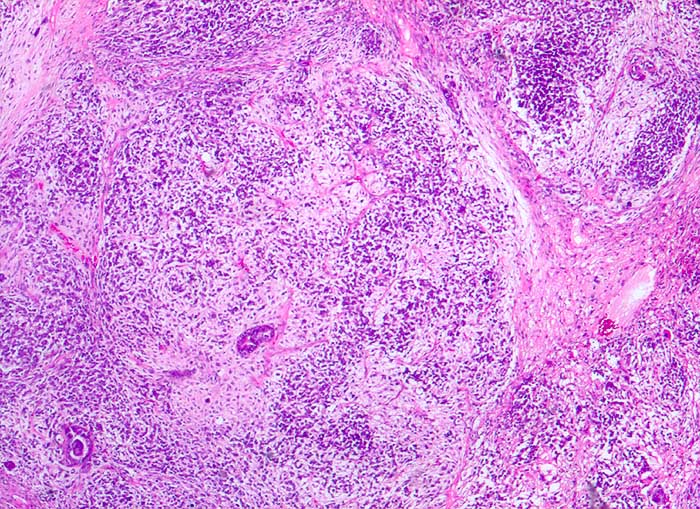

PathoPic ID 5386 - maligner Müller'scher Mischtumor des Ovars

maligner Müller'scher Mischtumor des Ovars

Ovar

Karzinomatöse Drüsen in malignem mesenchymalem Stroma

Ovarialkarzinom

Histologie

25